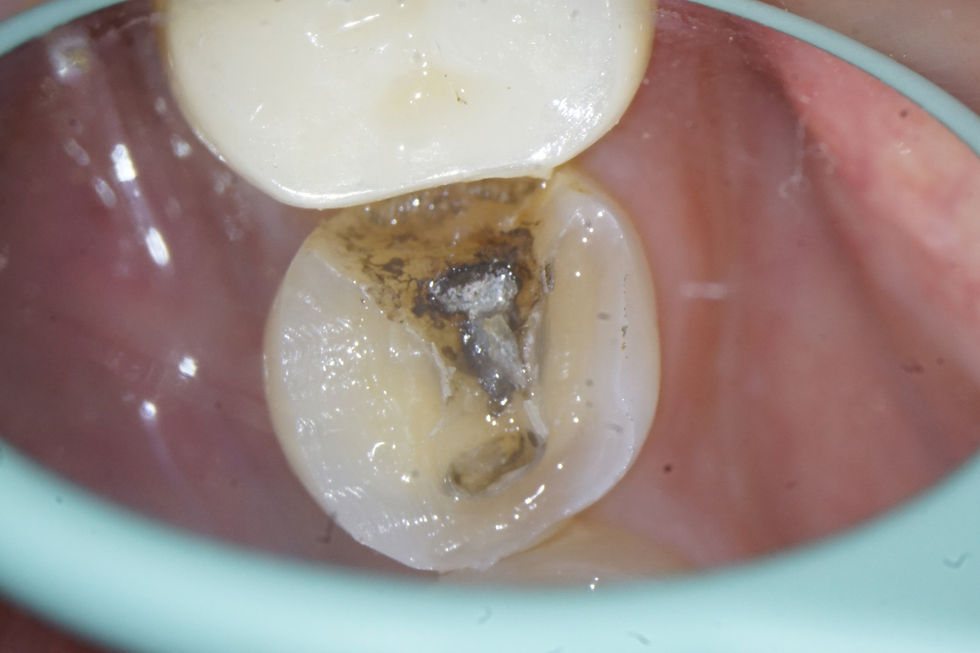

STM 3/4 Crown #45